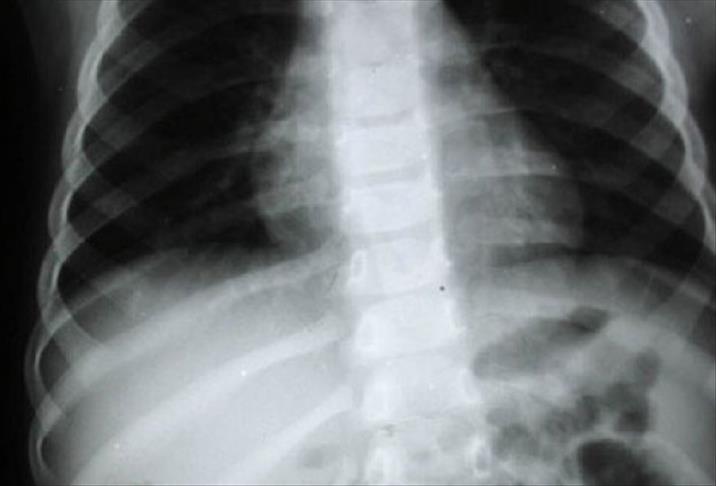

Tüm kanserler içinde özellikle akciğer kanserinde yaşam oranlarının istenilen düzeyde olmadığının altını çizen Gültekin, daha etkin tedavi için erken tanının önem taşıdığını belirtti. Gültekin, akciğer kanserinin genellikle ileri evrede kendini gösterdiğini ifade ederek, yurt dışında akciğer kanserine yönelik yeni tarama ve erken teşhis imkanı sunan metotların araştırıldığını söyledi.